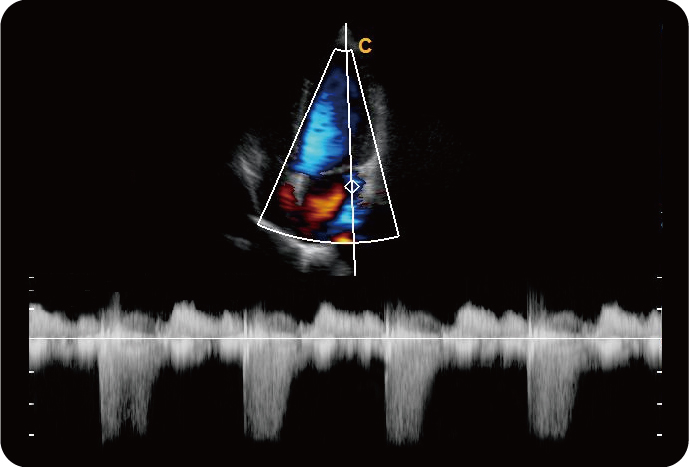

Секторный Фазированный